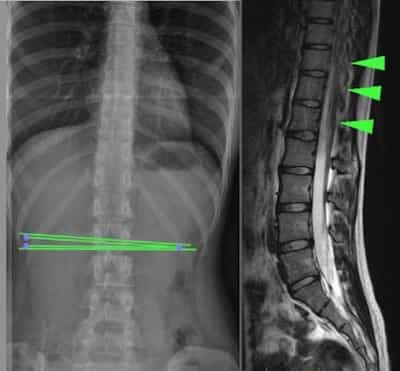

Occult tethered cord or “Occult Tethered Cord Syndrome” is associated with an occult spina bifida. This is a neuro-spinal malformation that is characterized by the incomplete development of the spinal cord (predominantly in the lumbar region) which is anchored by the malformation, producing mechanical injuries due to the traction, mainly in the spinal cord and spine (Fig.1).

To detect and diagnose it, it is necessary to perform complementary tests like a Nuclear Magnetic Resonance (MR) or a Computerized Axial Tomography (CT) or a simple X-ray of the spine level where the tethering is located.